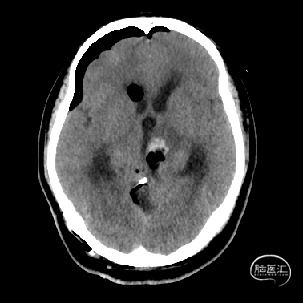

术后当天CT

术后1周CT复查